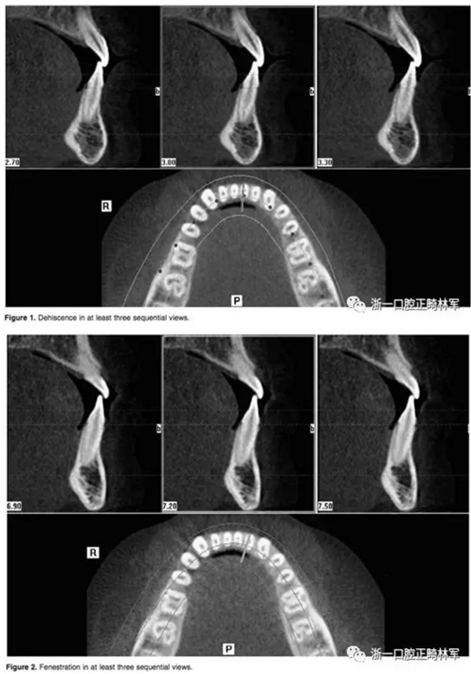

在iCAT配套軟件上進行數(shù)據(jù)的二次三維重建。這種二次重建能夠創(chuàng)建最大精度的三維圖像使我們能夠進行線性測量。每根牙根在軸向和橫斷面的切片上進行距離頰舌側(cè)牙槽骨距離的評估。在至少三個連續(xù)的視圖中,牙根周圍沒有皮質(zhì)骨的情況被認為是牙根周圍存在牙槽骨缺損。如果牙槽骨高度低于釉牙骨質(zhì)界超過2毫米,記為骨開裂。如果牙槽骨的缺損位于牙槽嵴下方而未至牙槽嵴頂,記為骨開窗。